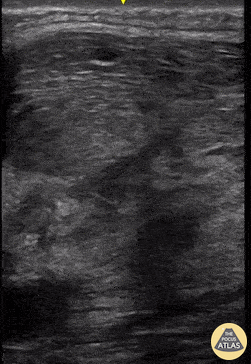

Musculoskeletal - Pyomyositis

A 35 year-old-male presented with neck pain and a history of recurrent neck abscesses. Prior treatment had included I&D. Soft-tissue POCUS was notable for appearance of muscle inflammation without focal fluid collection; subsequent operative findings confirmed pyomyositis of the right neck including sternocleidomastoid muscle. Brian Toston, Internist. Aventura, FL